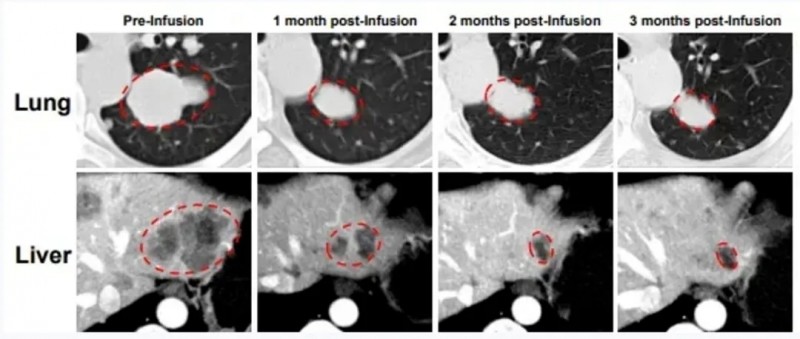

2024年ASCO大会上,公布了GT201的Ⅰ期研究(NCT05729399)的振奋数据,展现出良好的疗效与安全性。该研究共入组7例实体瘤患者(包括非小细胞肺癌、恶性黑色素瘤、卵巢癌、宫颈癌),中位年龄为48岁,既往平均接受3种治疗。入组后,接受标准FC淋巴细胞清除+GT201回输治疗。

结果显示:全部入组患者中,42.9%(3例)达部分缓解(PR),28.6%达病情稳定(SD);非小细胞肺癌(NSCLC)亚组中,疾病控制率竟高达100%(SD>24周或PR)。此外,GT201在患者体内强劲扩增,输注后至少6个月仍存于外周血。

值得一提的是,其中1例获得部分缓解(PR)的患者,GT201治疗后疗效显著,Virchow's淋巴结(左侧锁骨上窝淋巴结)靶病变从治疗前46.7mm,在GT201治疗后第4个月时显著缩小69%(详见下图)。

▲图源“ASCO”,版权归原作者所有,如无意中侵犯了知识产权,请联系我们删除